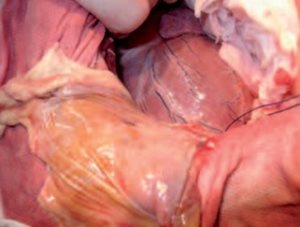

Le nerf phrénique est repéré et protégé, une incision longitudinale du sac est réalisée ventralement au nerf sur toute sa longueur. La section est ensuite poursuivie du côté gauche, de manière à retirer la plus grande quantité de sac possible et à extraire la coupole ventrale en une seule partie (photo 5).

Photo 5. Solement et ligature du péricarde.